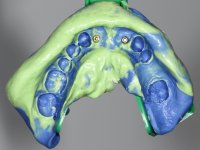

After an imaging study, the placement of two implants of 3.3 mm in diameter and 10 mm in length was planned. On the day of surgery, teeth 42 and 32 were extracted and the implant was removed. The implants were placed in the area of the alveoli, taking care to slightly lingualize their positioning. An impression was made using the open tray technique with the flap open for the fabrication of the immediate provisional bridge. While the impression was taken to the laboratory, tall healing screws were placed and the surgical wound was sutured. The patient waited 2 hours in the waiting room while the temporary bridge was made in the laboratory. An immediate screw-retained provisional bridge was placed and its seating was controlled by imaging. After 3 months, the final impression was made using an open tray technique. In this consultation, we took the opportunity to polish the temporary bridge with rubber cups so that the soft tissues could mature in better conditions. Information was collected to better characterize the monolithic structure in Zr. Color guides were used for the coronal and gingival ceramics. In the laboratory, a bridge was made in Zr. bolt-on that has been carefully characterized. After approval by the patient, it was definitively placed in the mouth. Tightening was performed with a dynamic wrench with a torque of 35 N. The holes were covered with Teflon and filled with composite resin.